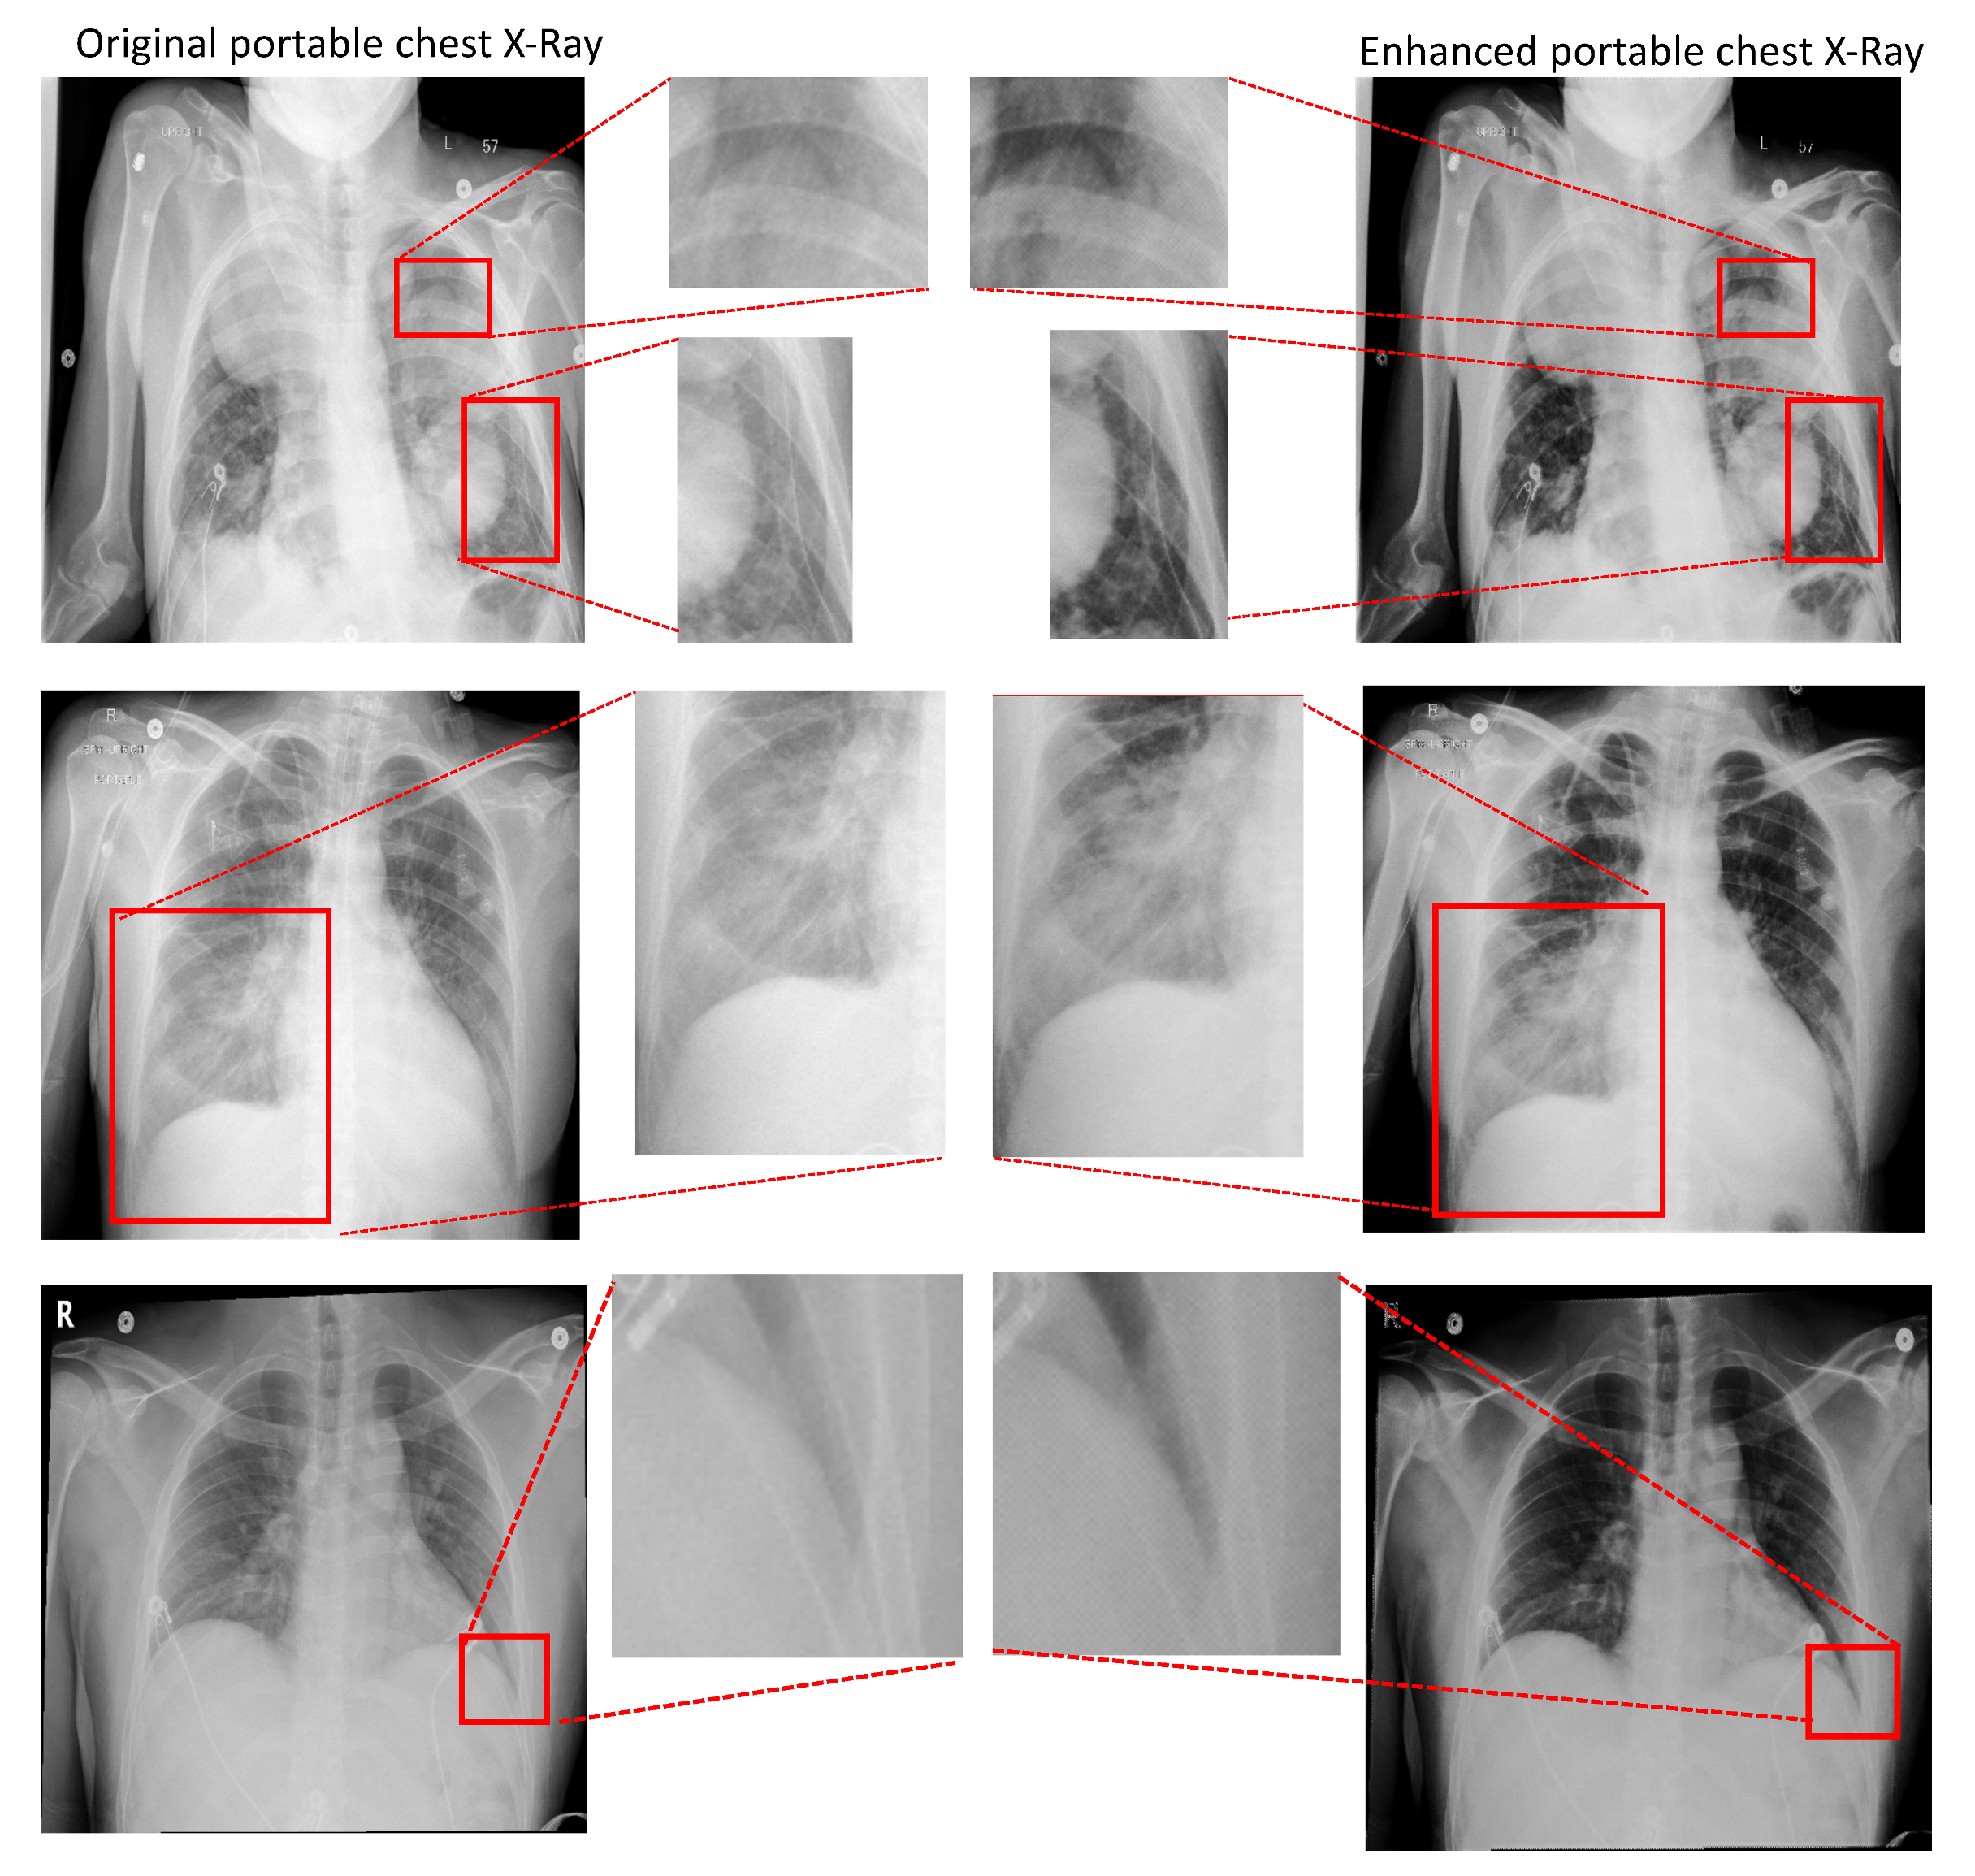

- Thirdly, we propose a new PairFlow approach, an end-to-end invertible transfer of a deep learning method, to enhance the degraded CXRs from the portable machine. High-quality knowledge is then transferred to a degraded domain to increase the portable CXRs quality.

3.2. Portable Radiograph Quality Enhancement

4.3.2. Portable Radiographs Quality Enhancement

| RoIs | PSNR ↑ | SSIM ↑ | ||

|---|---|---|---|---|

| Por.CXR vs. Con.CXR | Enh.CXR vs. Con.CXR | Por.CXR vs. Con.CXR | Enh.CXR vs. Con.CXR | |

| 28.019/0.245 | 30.273/1.798 | 0.936/0.018 | 0.960/0.011 | |

| 28.003/0.236 | 30.437/1.707 | 0.748/0.047 | 0.787/0.045 | |

| 29.009/0.229 | 30.474/1.724 | 0.919/0.021 | 0.955/0.013 | |

| 28.006/0.227 | 30.522/1.662 | 0.729/0.050 | 0.780/0.047 | |

| 28.011/0.205 | 30.407/1.670 | 0.873/0.035 | 0.920/0.021 | |

| 28.009/0.198 | 30.498/1.629 | 0.839/0.044 | 0.910/0.026 | |